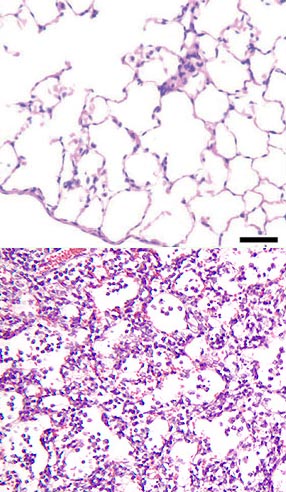

Krupoz, ocaqlı, intersisial və s. formaları var. Krupoz pnevmoniya kəskin ağciyər xəstəliyidir, bakterial pnevmoniyaların ən təhlükəlisidir. Krupoz pnevmoniyada ağciyərin bir, bəzən də bir neçə payında patoloji dəyişiklik olur; xəstəliyi, əsasən, pnevmokoklar törədir. Xəstəlik başağrısı, yüksək hərarət (39–40°S), quru və bəlğəmli öskürəklə başlayır, döş qəfəsi sancır (öskürdükdə və dərin nəfəs aldıqda artır). Xəstəliyin ikinci günündən başlayaraq selikli bəlğəm ifraz olunur. Sonralar qan qarışdığından bəlğəm pas rəngi alır. İlk günlər xəstənin yanaqları qızarır, dodağı, burnunun ucu, bəzən boyun və qulağı uçuqlayır; nəbzi dəqiqədə 100–120 vurur, arterial təzyiqi aşağı düşür. Yuxusu çəkilir, dilinin üstü quru ərplə örtülür, sayıqlama, iştahasızlıq, ürəkbulanma və qusma müşahidə olunur. Qanda leykositlərin sayı artır, eritrositlərin çökmə reaksiyası sürətlənir; sidiyin miqdarı azalır, xüsusi çəkisi isə artır. Krupoz pnevmoniyada bəzi ağırlaşmalar (məsələn, plevranın quru və ya eksudatlı iltihabı, ağciyərin irinləməsi, kollaps, ürək çatışmazlığı və s.) müşahidə oluna bilər.

İnterstisial pnevmoniyada iltihab prosesi ağciyərin birləşdirici ara toxumasında gedir. Həmin xəstəlik ağciyər iltihabının başqa formalarına nisbətən uzun sürür.